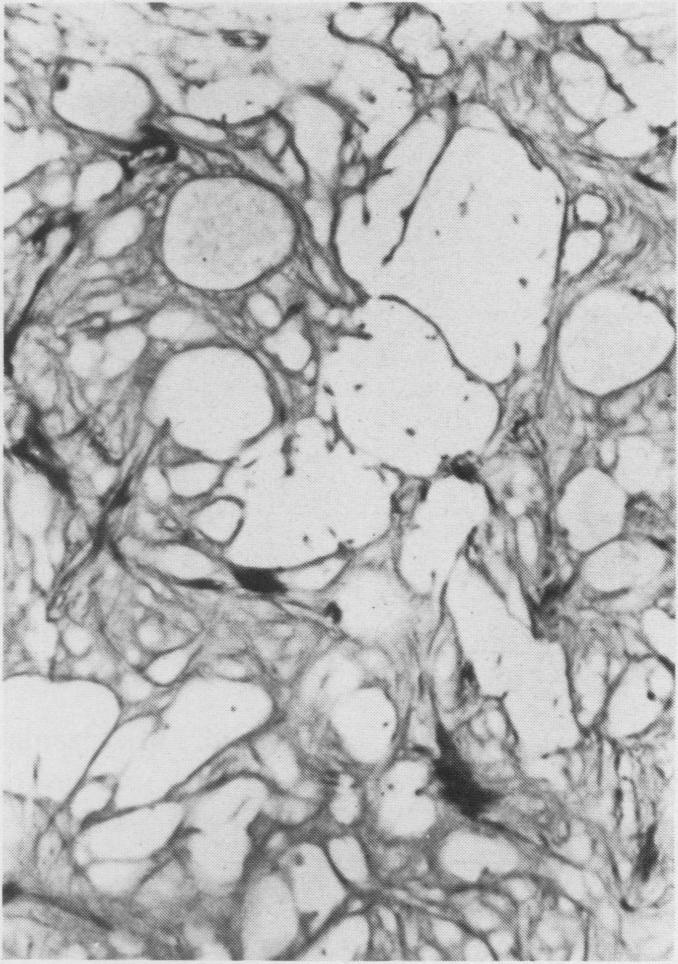

Necrosis of intramedullary bone and bone marrow elements is reported in the long bones of a dog. Radiographically lesions were evident as an irregular increase in intramedullary density. On gross postmortem examination necrotic tissue appeared as yellow-white deposits on the endosteal surface and in the medullary cavity. Microscopically, necrotic bone had empty lacunae and was often covered by basophilic, woven bone. The cause and pathogenesisof aseptic necrosis of bone are discussed.